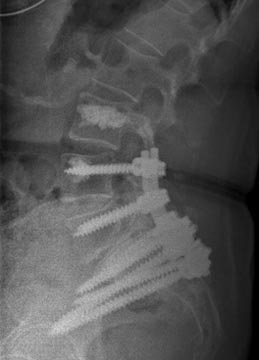

64 year old man with prostatitis who developed osteomyelitis of T12/L1 treated with an all posterior approach thoracolumbar fusion and debridement with antibiotic cement.